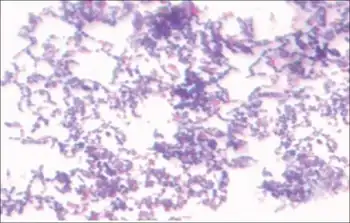

Stain of S. mutans in thioglycollate broth culture.

Gram stained streptococcus mutans